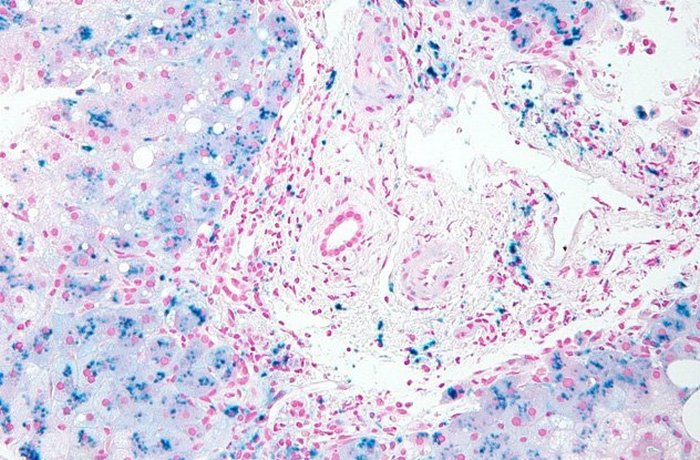

Гемохроматоз – это генетическое нарушение, которое приводит к чрезмерному накоплению железа в организме. «Перегрузка организма железом» настолько распространена в Ирландии, что стала известна как «кельтское проклятие». Генетический анализ показывает, что эта мутация была доставлена на остров в бронзовом века мужчиной, ДНК которого показало, что он был родом из понтийских степей. Исследователи сравнили генетику ирландской фермерши неолитического периода (которая умерла 5200 лет назад) и мужчины бронзового века мужчин, умершего 1200 лет спустя.

У темноглазой шатенки предки явно были охотниками-собирателями преимущественно ближневосточного происхождения. Люди бронзового века уже имели гены голубых глаз (наиболее распространенную Y-хромосому в современной Ирландии), были не настолько восприимчивы к лактозе и имели мутировавший ген C282Y, ведущий к «кельтскому проклятию». Сильная разница в генетике предполагает, что Ирландия столкнулась с периодом сильной миграции.